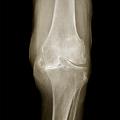

Gonarthrose

Image